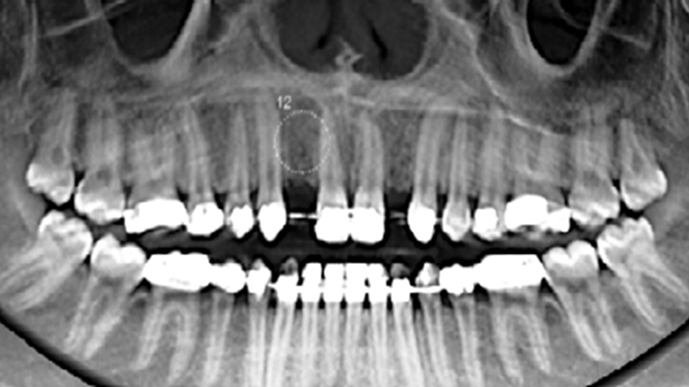

Clinical case: 3.0 mm MiNi implants placement at #12, #22

- Courtesy of Dr. Achraf Souayah, Tunise -

Keywords

Anterior esthetics, MiNi, flap elevation, minimally invasive technique, soft tissue management, esthetic zone, Dr. Achraf Souayah, anterior aesthetics, aesthetic, aesthetics, esthetic, #12, #22

Products:

MiNi implant system